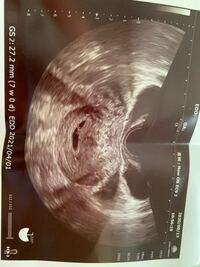

7週 胎芽見えない 妊娠7週目・胎嚢・見えないに関するみんなの口コミ・体験談 妊娠7週目・胎嚢・見えないについてママリに寄せられた疑問を集めてみました!妊娠6週(6w)初診受診!胎嚢の大きさや心拍確認 妊娠2ヶ月(妊娠4週、5週、6週、7週)の胎児と 妊娠検査薬で陽性反応確認!産婦人科の初診はい 妊娠6週 胎芽が見えない ゆる子育て日記 妊娠6週目で初診 – めぐブロ。 妊娠6週0日(6w0d)の超音波胎嚢見えない。 5w4d ひとり言、妊活ブログ 19年09月05日 1751 9月3日 (火)病院に行って来ました。 先生に少量の出血があり生理だと思ってたら妊娠検査薬に陽性反応があったと伝えエコーで診てもらうも胎嚢見えず。 先生は更に首をかしげる。 『うーん

現在 妊娠6週と6日)で胎嚢mmで本日産婦人科医より「胎芽が見えない」旨の診断結果を言渡されており、大変心配致しております。 ポプラさんと同様に来週再度診断が必要な様です。 (尚、昨年・一昨年と続けて流産しており今回はアスピリン治療を 妊娠7週以降で胎嚢は見えているのに胎芽やその 心拍が確認できなかったり、一度は確認できた心拍が消えてしまった場合には、「 稽留流産 」の可能性があります。10月25日に胎嚢を3ミリで確認できました。 11月7日に行ったら胎嚢は11ミリでしたが赤ちゃんは見えず、、、、、 つわりなどはあるのですがとても不安です (;_ 同じような方いらっしゃいますか? 不順なため、週数がわからないのですがおさらく5〜7週なの

妊娠6週で胎嚢が見えない、7週でも心拍が確認できなかった話 狐の嫁入り 娘を妊娠したときのお話です タイトル通り、 娘ちゃんは胎嚢確認も、心拍確認も遅くてとても不安でした 暇さえあればネットサーフィンの毎日 そのとき見つけた kitsuneyomeiricom 7週0日で胎芽心拍あるが、大きさが1ミリもない時の成長の可能性 不妊治療に通い、タイミング治療中の妊娠でした。 なので、排卵日は間違いないと思います。 5週0日で胎嚢確認8.1ミリ。 6週0日で胎嚢12.3ミリ胎芽1ミリ未満、心拍確認。 妊娠7週2日 胎嚢のみ 胎芽が見えない *yurire*lalaブログ 〜ファッション、子育て、好きな事〜 17年08月17日 1029 昨日、産婦人科に行ってきました主人もお休みだったので、心拍確認出来るのを楽しみに行ったんですが、診察の結果、エコーで見れたのが

やっぱりすることと言えば、 『妊娠7週 赤ちゃん見えない』 をググる、ググる。 稽留流産についてのブログも読みました。 関係ないと思ってた。 まさか自分がその状況に置かれるとは。 何よりも、自分が一番気付いてしまっているのが、 昨日まで妊娠4週になると見えてくる、「胎嚢」「卵黄嚢」って何? 妊娠5週になると脳や神経、心臓など臓器、それに手足や目、耳の原型もできるってホント? 妊娠6~7週で、心臓の動き出す!? まだ「胎児」と呼んでもらえない妊娠2ヶ月の「胎芽」時代の赤ちゃんのこと、母体のこと。 7週で潰れた胎嚢と血の塊。 8週で胎嚢はmmに成長したものの、胎嚢の中に何も見えず。 9週でmmの胎芽を確認、心拍も確認 したとのことです。 生理予定日からの計算で